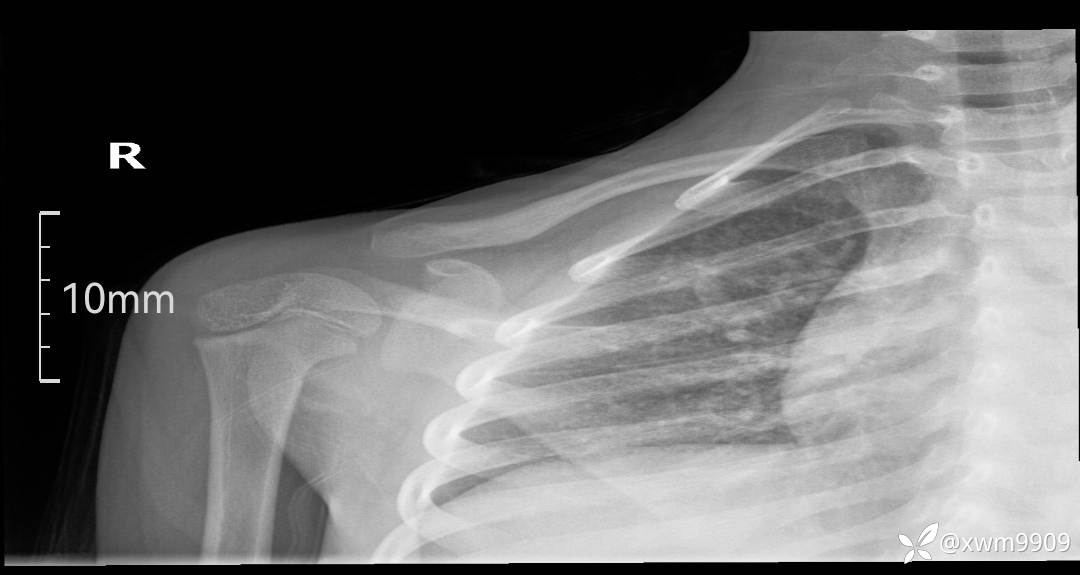

2024-03-19,门诊“摔伤右锁骨肿胀疼痛6小时。拟“锁骨骨折”要求摄:右肩关节正侧位,右锁骨轴位检查。

DR: